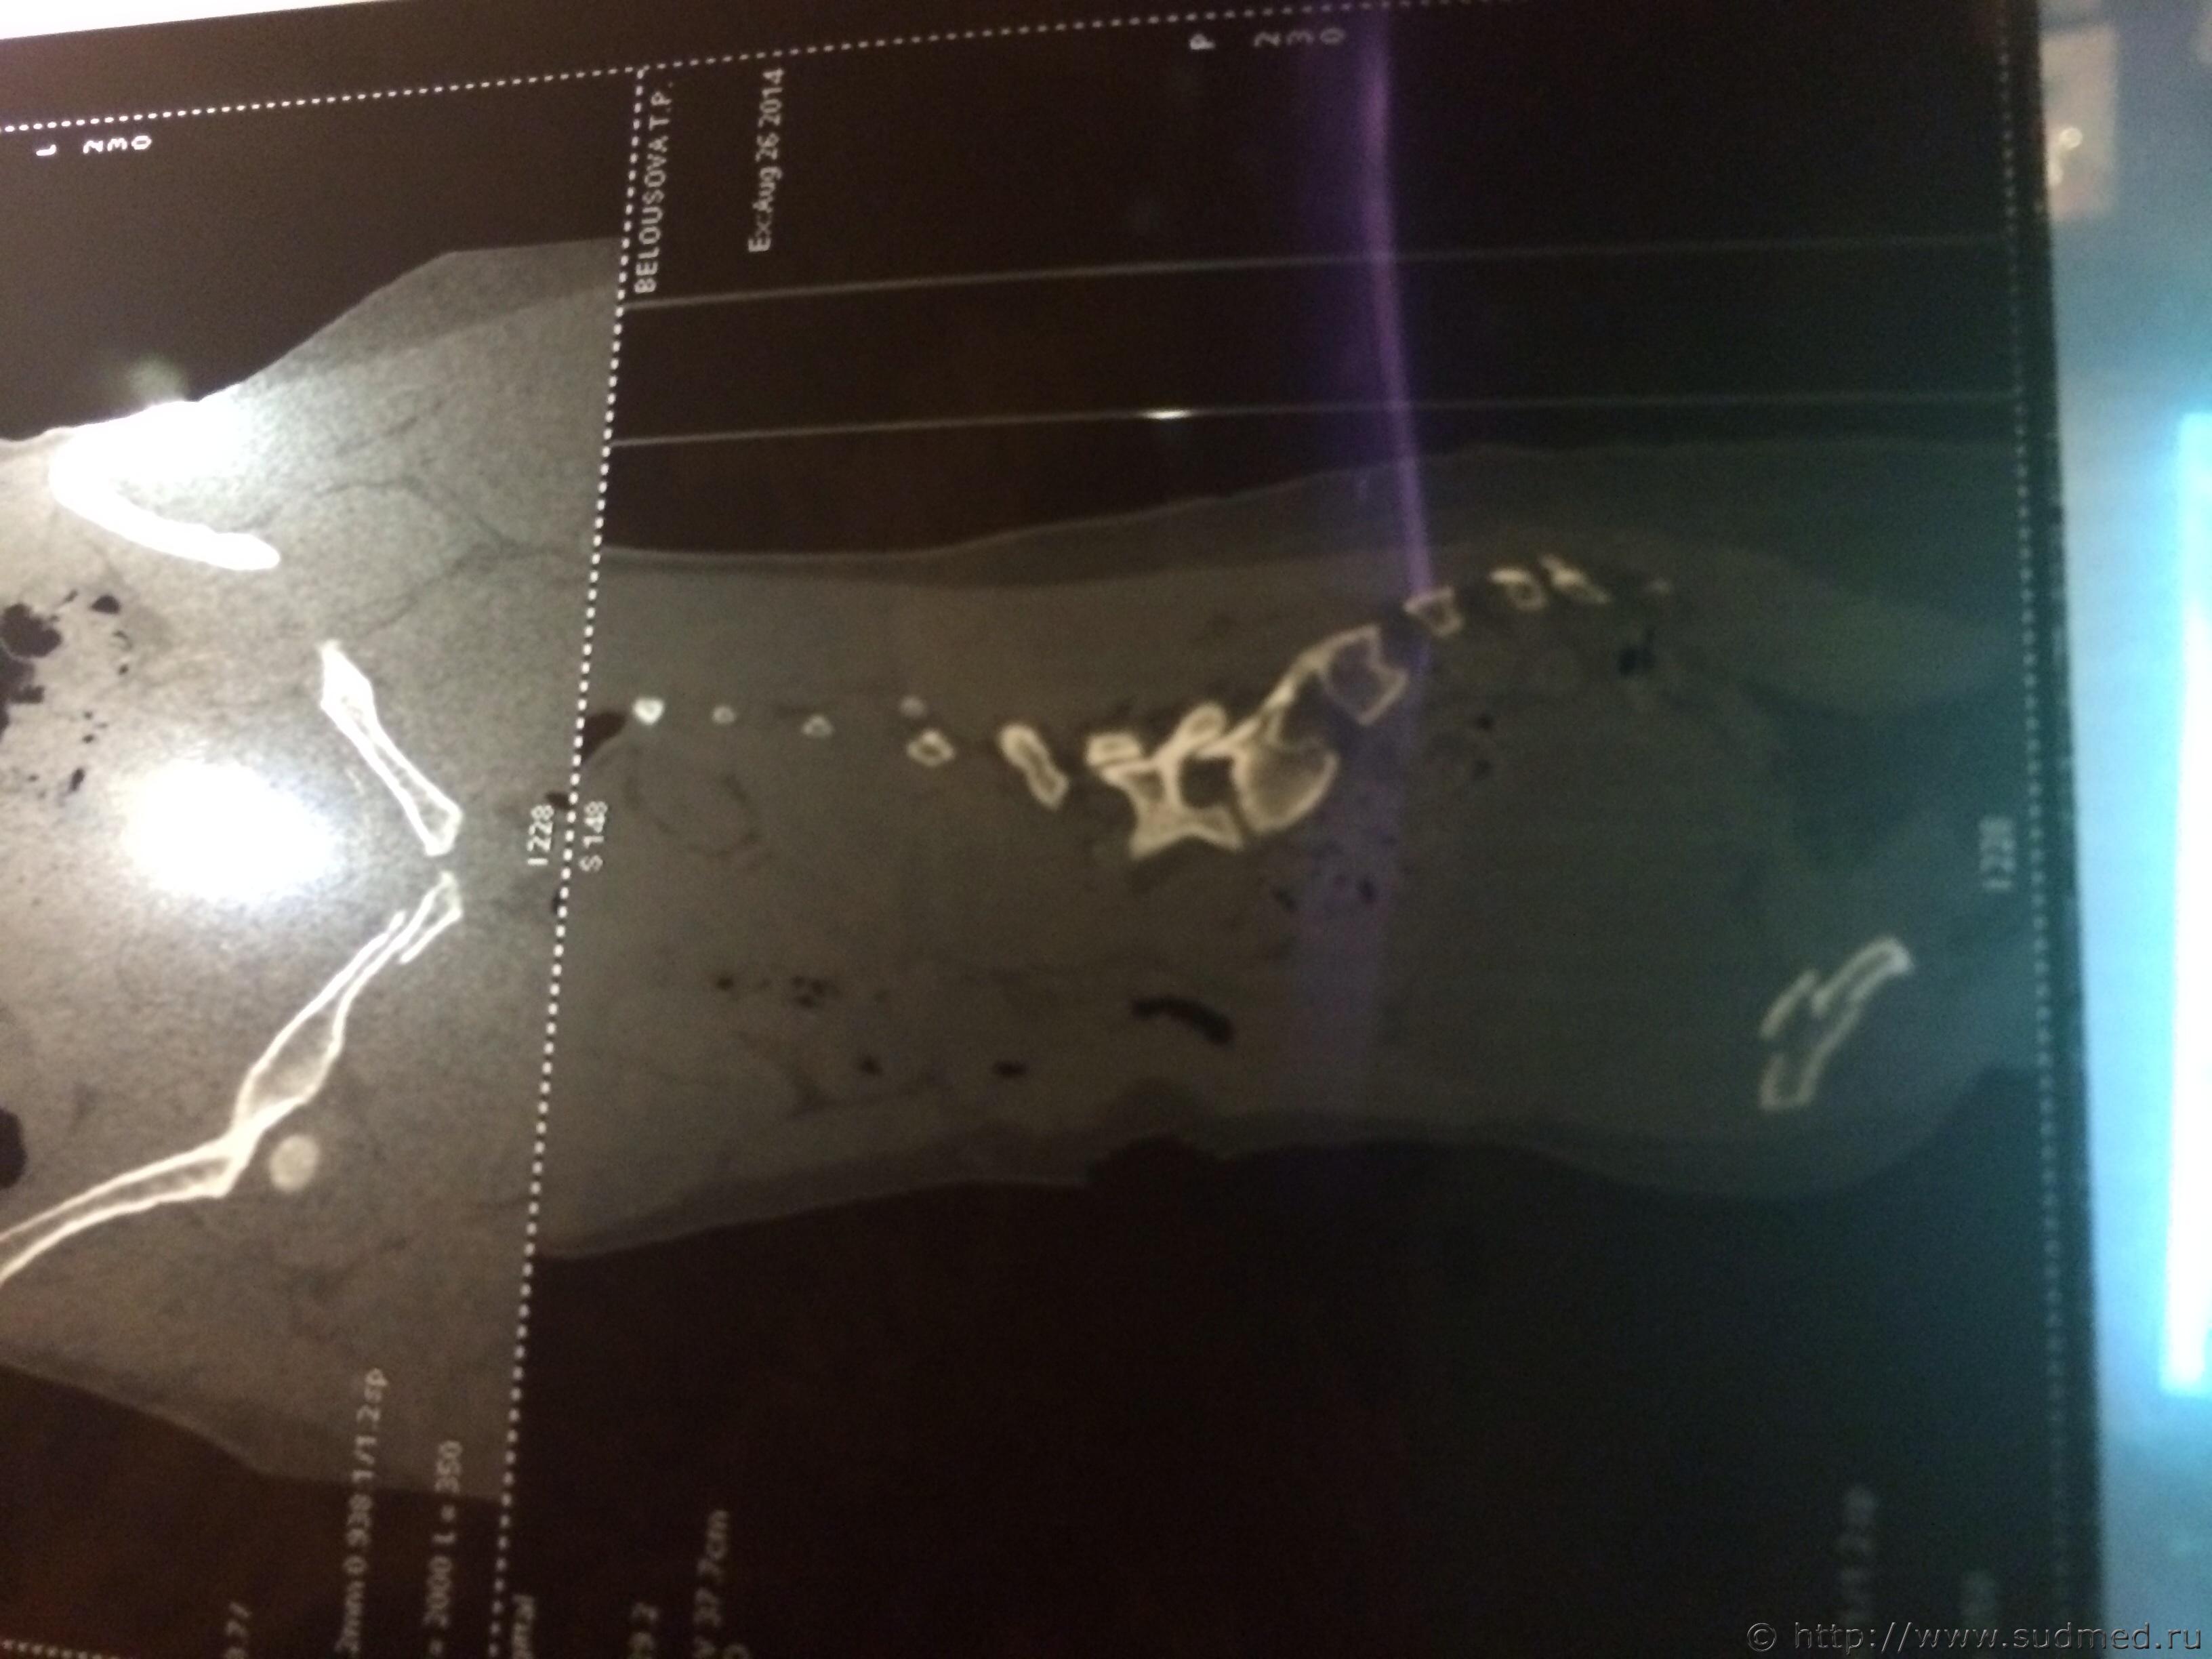

Спасибо! У меня результаты КТ, ошиблась)

КТ

Как мне видится - вертикальный перелом крестца. Тяжкий вред.

Впрочем, оставляю небольшую вероятность, что я не видел все сканы, да и качество их здесь, разумеется, хуже, чем изображение на пленке или на экране компьютера у врача, работающего на томографе.